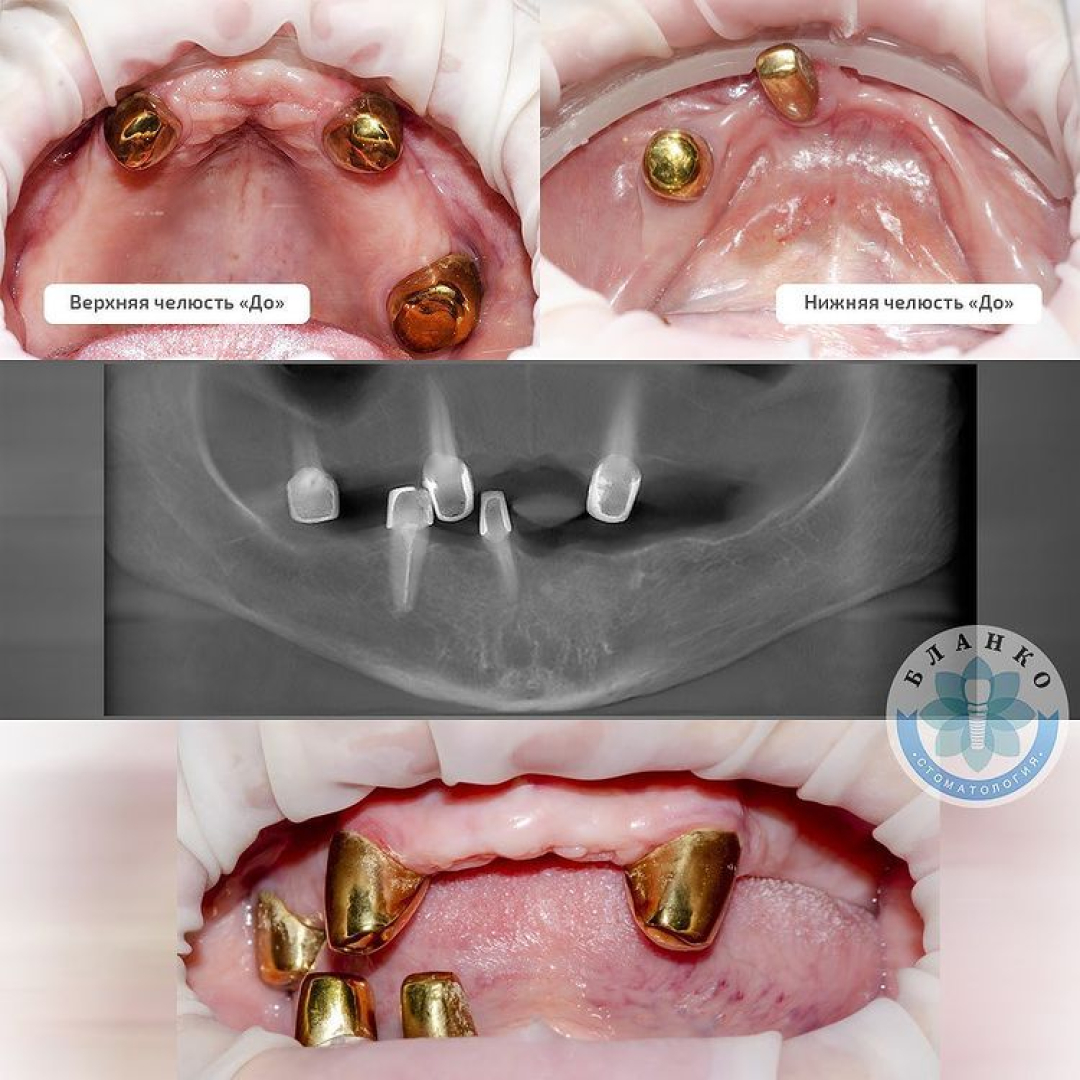

В данной ситуации в первое посещение были удалены оставшиеся зубы, пораженные пародонтитом ( 5 штук ).

Сразу установлено 10 имплантов.

Сделаны временные протезы на имплантах.

Через 4 месяца постоянное протезирование двумя несъёмными конструкциями на верхней и нижней челюсти.